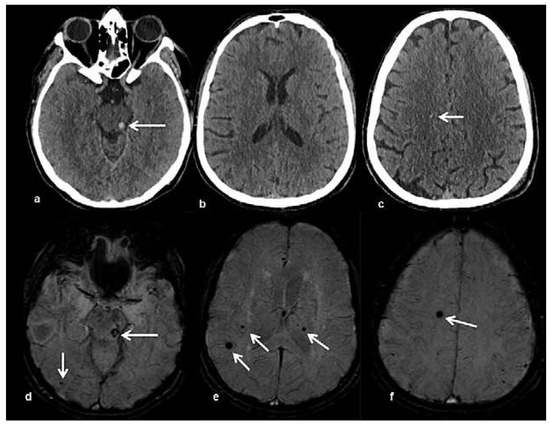

Head and brain trauma: general aspects and neuroimaging

by Johanna Maria Lieb, Christoph Stippich and Meritxell Garcia

In this article the general clinical aspects, imaging indications and different injury mechanisms of traumatic brain injury (TBI) are reviewed. In addition, the different imaging modalities and strategies are presented, including more specific imaging features of the various injuries. Computed tomography (CT) is [...] Read more.

In this article the general clinical aspects, imaging indications and different injury mechanisms of traumatic brain injury (TBI) are reviewed. In addition, the different imaging modalities and strategies are presented, including more specific imaging features of the various injuries. Computed tomography (CT) is the imaging modality of choice in the acute phase owing to its wide availability and short scanning time, as well as to its high sensitivity for the detection of fractures and acute bleeding. Although magnetic resonance imaging (MRI) is superior to CT in many other aspects, it plays no role in the acute phase. MRI, however, has been proven to be useful and complementary to CT in the subacute and chronic stages as well as in the case of inconclusive results on initial CT. Especially the use of standard sequences like fluid attenuated inversion recovery (FLAIR), diffusion and susceptibility weighted imaging (DWI and SWI) have been shown to increase the diagnostic potency in diffuse axonal injury, in mild brain trauma and also in more chronic stages of TBI. The use of more advanced MRI techniques such as diffusion tensor imaging (DTI), magnetic resonance spectroscopy (MRS), functional MRI (fMRI) and magnetic transfer imaging (MTI) can further complete the diagnostic evaluation and give insights into different pathophysiological processes in TBI. Full article